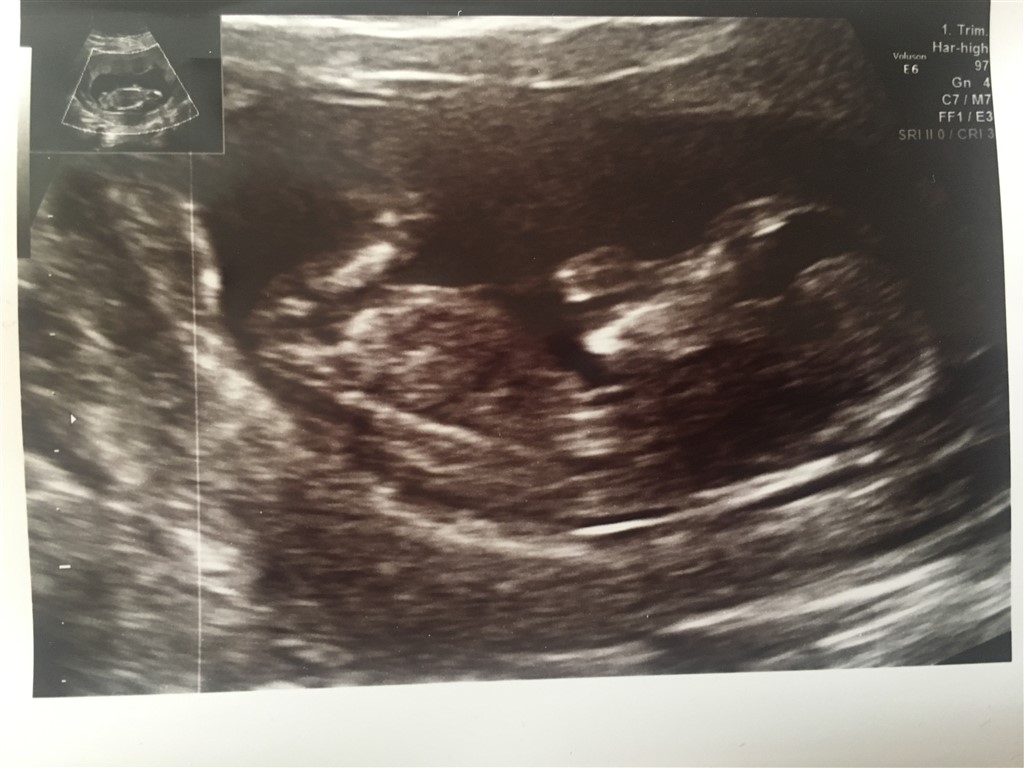

Må jeg spørge hvorfor? Eller er det bare en tanke? Jeg forstår nemlig ikke de streger man kigger efter

Ved en pige er der tre hvide streger, hvor den i midten er mindst, og minder om en burger.

ved drenge er der kun to streger.

giver det mening! ?